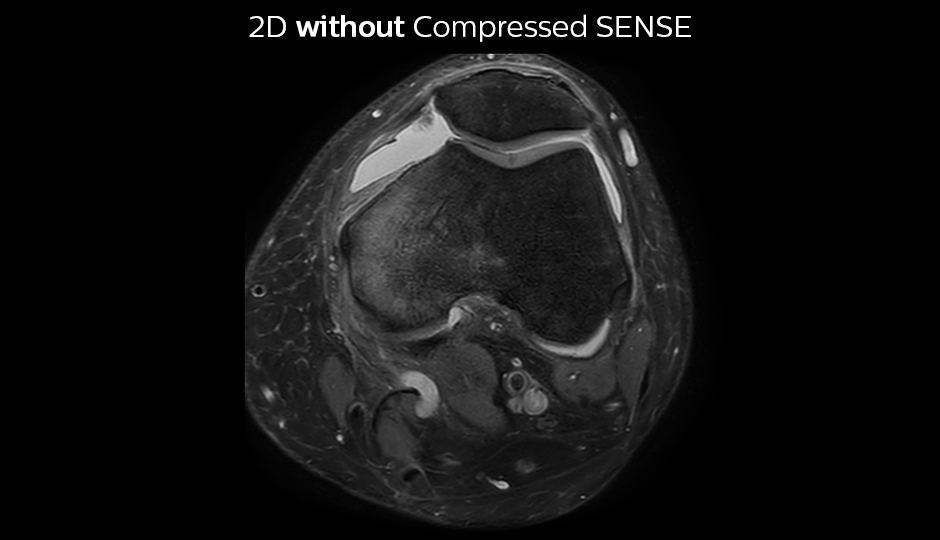

Comparing 2D with 3D using Compressed SENSE

A good acquisition time with high resolution is obtained when moving from three 2D acquisitions in three planes to one 3D acquisition with Compressed SENSE. In this example, Compressed SENSE with 3D VIEW PD SPAIR is 50% faster than three separate 2D scans and has improved spatial resolution.

Without Compressed SENSE Scan time 2:55 + 3:37 + 3:51 = 10:23 min. Voxel size 0.55 x 0.65 x 3 mm

Three separate 2D PD scans in three orientations

With Compressed SENSE factor 10 Scan time 5:03 min. Voxel size 0.6 x 0.6 x 0.6 mm

3D VIEW PD SPAIR high resolution knee